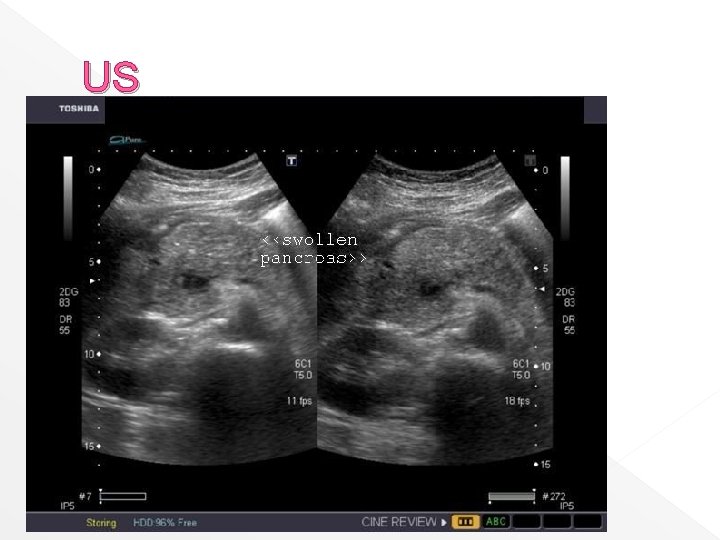

Acute pancreatitis Severity of acute pancreatitis ranges mild edema with minimal symptoms to a severe necrotizing process that culminates in multiple organ failure US and CT most precisely define the anatomic extent of the lesions and the detect local complications

US finding: › The acutely inflamed pancreas enlarged with decreased echogenicity and blurred irregular margin › Fluid collection are seen as hypoechoic areas › US can be used to guide aspiration and the drainage procedures, and for follow up

US